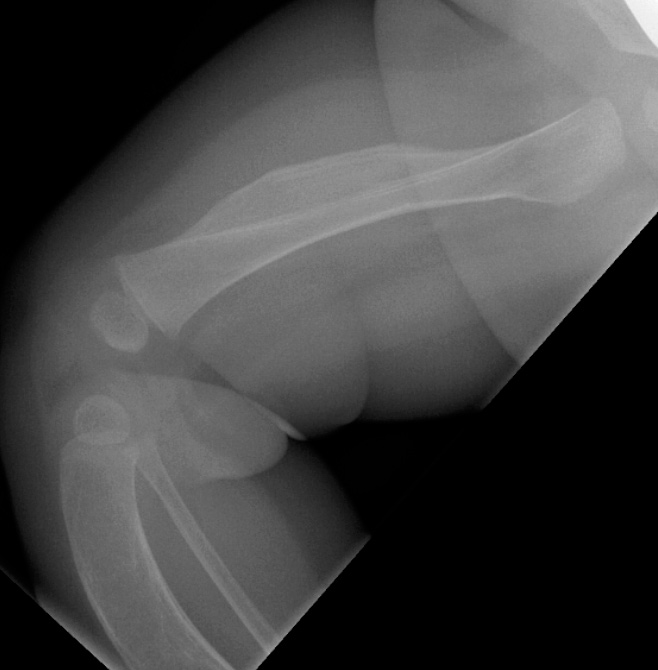

En tre måneder gammel jente ble henvist med spørsmål om tumor på låret. Barneradiolog fant ved ultralydundersøkelse distinkt ømhet og bløtvevsødem foran på høyre lår, men ingen bløtdelstumor. Supplerende røntgenundersøkelse viste fortykkelse av corticalis (kortikal hyperosteose) i høyre femurdiafyse (bildet til venstre), anterior krumming av begge tibiae med brede, oppdrevne diafyser og fortynnet corticalis. Tilsvarende forandringer ble funnet i høyre femur. Krumningen av tibia ses tydelig på lysbildet til høyre.

Pasientens far og farmor ble født med liknende legger – hos begge var det spontan bedring i løpet av et par år. Røntgenopptak av farens legger viste antydet anterior krumming av begge tibiae, med noe utvisket kortikomedullær grense i diafysene.

Sykehistorie og røntgenfunn var forenelig med Caffeys sykdom, infantil kortikal hyperostose, som er karakterisert ved subperiostal beinnydanning som oftest involverer mandibula, de lange rørknoklene, clavicula og ribbein.